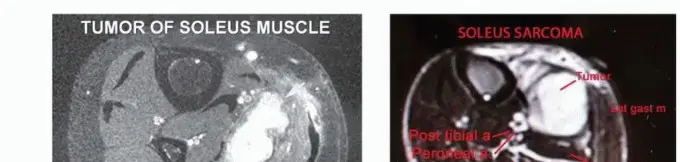

صورة توضيحية لورم في قصبة الساق القريبة.

صورة شعاعية تظهر ساركوما عظمية في قصبة الساق القريبة لمريضة تبلغ من العمر 17 عاماً.

صورة شعاعية توضح ورماً عظمياً في قصبة الساق القريبة.

صورة شعاعية تظهر ورماً خلوياً عملاقاً في قصبة الساق القريبة.

صورة مقطعية توضح الورم الذي يملأ مشاش قصبة الساق القريبة.

صورة مقطعية أخرى للورم في قصبة الساق.

صورة شعاعية جانبية توضح ساركوما عظمية في قصبة الساق القريبة.

صورة بالرنين المغناطيسي تظهر مدى امتداد الورم داخل النخاع العظمي.

صورة شعاعية تظهر تدميراً قشرياً وامتداداً للأنسجة الرخوة للورم.

صورة مقطعية توضح تدميراً قشرياً وامتداداً للأنسجة الرخوة للورم.